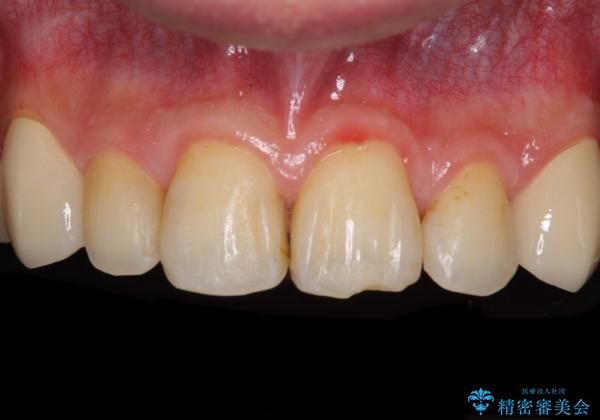

- 以前矯正を行った際に前歯が虫歯だらけとなり、審美面を気にして来院された患者様です。

虫歯の大きかった左右犬歯はオールセラミッククラウンで補綴治療をおこない、4前歯は研磨や古い充填物の詰め直しを行いました。

歯並びは良くなったものの、着色が気になって口元を見せることを躊躇していた用ですが、治療後は他人の視線を気にすることがなくなったようで、大変満足していただきました。